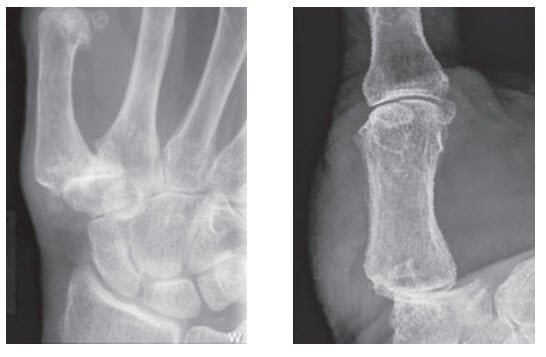

links: Frontansicht; rechts: Seitenansicht